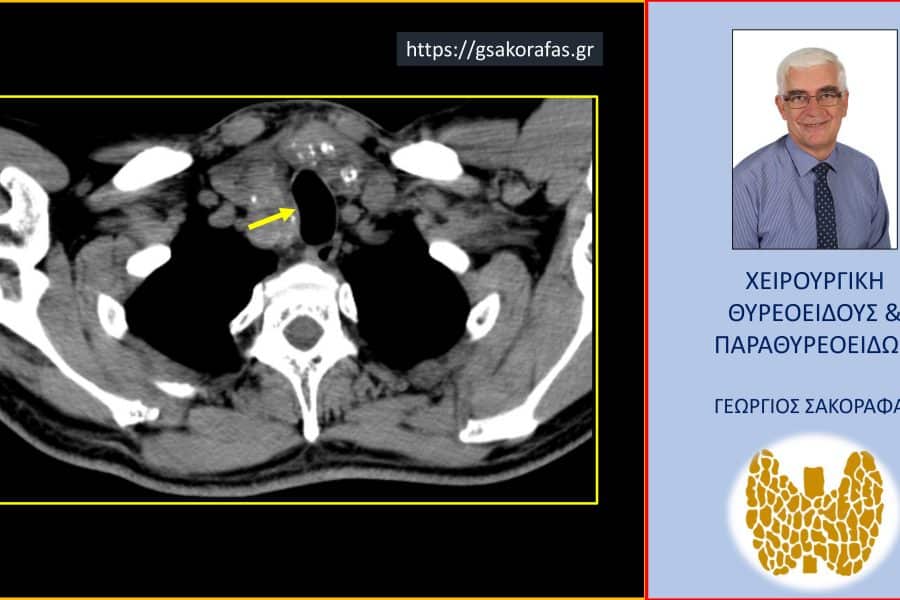

ΒρογχοκήληΚαταδυόμενη Βρογχοκήλη Ευμεγέθης καταδυόμενη βρογχοκήλη – Εικόνες (σε ασθενή μας) Ευμεγέθης καταδυόμενη βρογχοκήλη – Εικόνες (σε ασθενή μας) Ο ασθενής, ετών 57, προσήλθε για χειρουργική…George Sakorafas14 Αυγούστου 2024

ΒρογχοκήληΚαταδυόμενη Βρογχοκήληκαταδυόμενος όζος θυρεοειδούςΌζοι Θυρεοειδούς Καταδυόμενος όζος θυρεοειδούς – Εικόνες (σε ασθενή μας) Καταδυόμενος όζος θυρεοειδούς – Εικόνες (σε ασθενή μας) Ο ασθενής ηλικίας 79 ετών προσήλθε για…George Sakorafas4 Απριλίου 2024

ΒρογχοκήληΚαταδυόμενη Βρογχοκήληκαταδυόμενος όζος θυρεοειδούςΌζοι Θυρεοειδούς Όζος θυρεοειδούς καταδυόμενος σε βάθος μέχρι κάτωθεν του αορτικού τόξου– αφαίρεση μέσω τραχηλικής τομής σε ασθενή μας Όζος θυρεοειδούς καταδυόμενος σε βάθος μέχρι κάτωθεν του αορτικού τόξου– αφαίρεση μέσω τραχηλικής τομής σε…George Sakorafas22 Φεβρουαρίου 2024

Καταδυόμενη Βρογχοκήλη Ευμεγέθης καταδυόμενη βρογχοκήλη – με αφορμή ασθενή μας (εικόνες) Ευμεγέθης καταδυόμενη βρογχοκήλη – με αφορμή ασθενή μας (εικόνες) Η ασθενής, ετών 60, προσήλθε για…George Sakorafas21 Φεβρουαρίου 2024